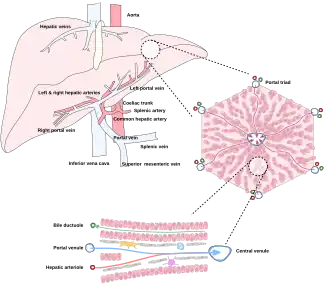

The liver is connected to two large blood vessels: the hepatic artery and the portal vein. The hepatic artery carries oxygen-rich blood from the aorta via the celiac trunk, whereas the portal vein carries blood rich in digested nutrients from the entire gastrointestinal tract and also from the spleen and pancreas.[11] These blood vessels subdivide into small capillaries known as liver sinusoids, which then lead to hepatic lobules.

Hepatic lobules are the functional units of the liver. Each lobule is made up of millions of hepatocytes, which are the basic metabolic cells. The lobules are held together by a fine, dense, irregular, fibroelastic connective tissue layer extending from the fibrous capsule covering the entire liver known as Glisson's capsule after British doctor Francis Glisson.[4] This tissue extends into the structure of the liver by accompanying the blood vessels, ducts, and nerves at the hepatic hilum. The whole surface of the liver, except for the bare area, is covered in a serous coat derived from the peritoneum, and this firmly adheres to the inner Glisson's capsule.

Microscopically, each liver lobe is seen to be made up of hepatic lobules. The lobules are roughly hexagonal, and consist of plates of hepatocytes, and sinusoids radiating from a central vein towards an imaginary perimeter of interlobular portal triads.[24] The central vein joins to the hepatic vein to carry blood out from the liver. A distinctive component of a lobule is the portal triad, which can be found running along each of the lobule's corners. The portal triad consists of the hepatic artery, the portal vein, and the common bile duct.[25] The triad may be seen on a liver ultrasound, as a Mickey Mouse sign with the portal vein as the head, and the hepatic artery, and the common bile duct as the ears.[26]

Histology, the study of microscopic anatomy, shows two major types of liver cell: parenchymal cells and nonparenchymal cells. About 70–85% of the liver volume is occupied by parenchymal hepatocytes. Nonparenchymal cells constitute 40% of the total number of liver cells but only 6.5% of its volume.[27] The liver sinusoids are lined with two types of cell, sinusoidal endothelial cells, and phagocytic Kupffer cells.[28] Hepatic stellate cells are nonparenchymal cells found in the perisinusoidal space, between a sinusoid and a hepatocyte.[27] Additionally, intrahepatic lymphocytes are often present in the sinusoidal lumen.[27]